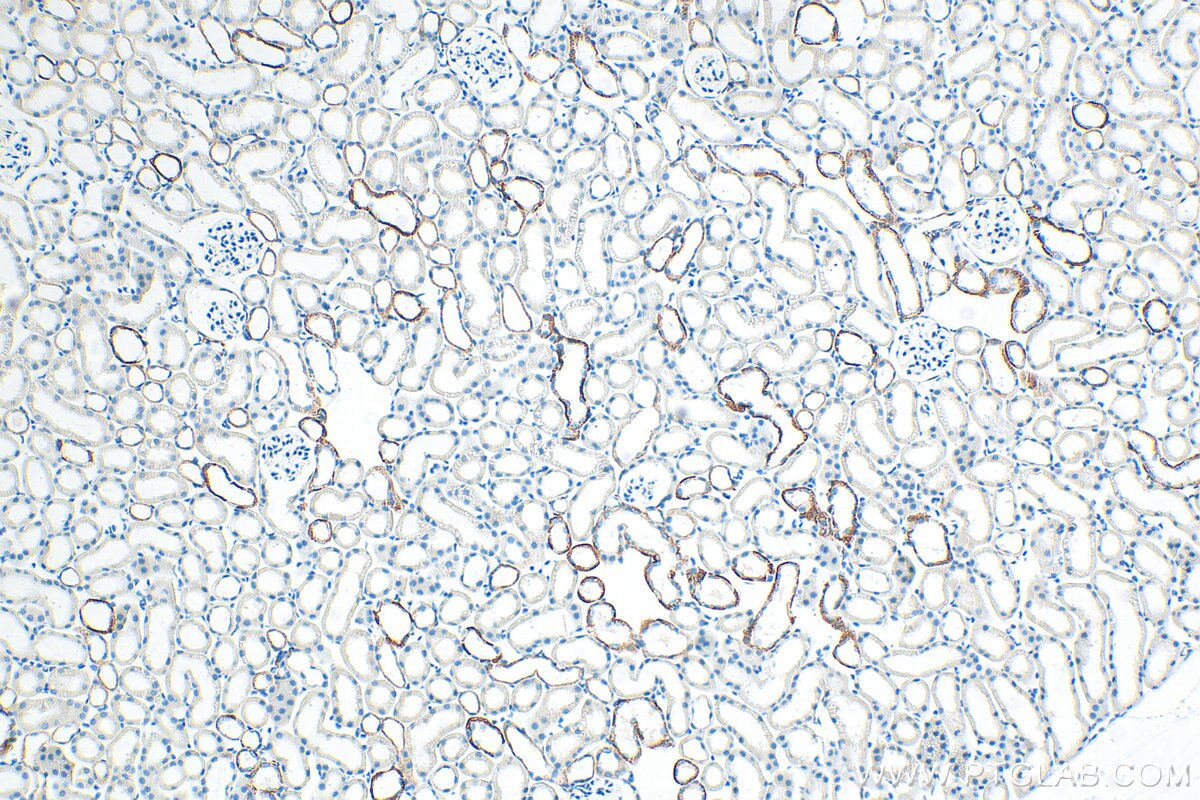

| Positive IHC detected in | mouse kidney tissue Note: suggested antigen retrieval with TE buffer pH 9.0; (*) Alternatively, antigen retrieval may be performed with citrate buffer pH 6.0 |

| Immunohistochemistry (IHC) | IHC : 1:200-1:800 |